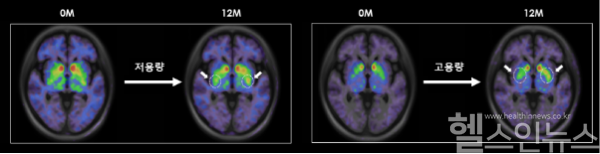

NMSS(비운동성 증상) 척도에서도 두 그룹 모두 각각 29.2%, 32.8% 개선 효과를 보였고, 뇌영상에서는 고용량군에서 더 높은 도파민 세포 생착 신호가 관찰됐다. 이는 TED-A9가 뇌 속에서 생존하고 도파민 신경세포로 성숙해, 파킨슨병의 근본적인 치료 메커니즘에 대한 강력한 증거를 제시한다.